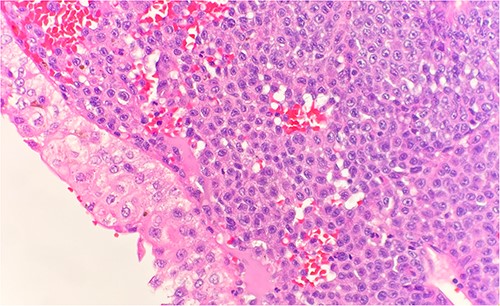

Immunohistochemical stains demonstrate the tumor cells to be strongly positive for vimentin, pankeratin, CK7, CK20, chromogranin, synaptophysin, CD45, and focally positive for CD56. Additionally, there were strongly and diffusely positive findings for S100 (Fig. 3), SOX10, and PRAME. Ki67 shows increased proliferative activity at estimated 25–30%. CD99 shows weak and patchy membranous staining while CK-PAN, p63, desmin, and smooth muscle actin are negative. The described morphology and immunoprofile are consistent with malignant melanoma.

Microscopic examination reveals sheets of round are positive for S100. IHC stain 40×.